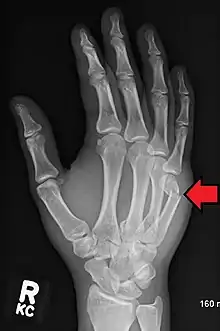

A boxer's fracture is the break of the 5th metacarpal bones of the hand near the knuckle.[4] Occasionally it is used to refer to fractures of the 4th metacarpal as well.[1] Symptoms include pain and a depressed knuckle.[2]

Classically, it occurs after a person hits an object with a closed fist.[3] The knuckle is then bent towards the palm of the hand.[3] Diagnosis is generally suspected based on symptoms and confirmed with X-rays.[3]

Diagnosis by a doctor's examination is the most common, often confirmed by x-rays. X-ray is used to display the fracture and the angulations of the fracture. A CT scan may be done in very rare cases to provide a more detailed picture.